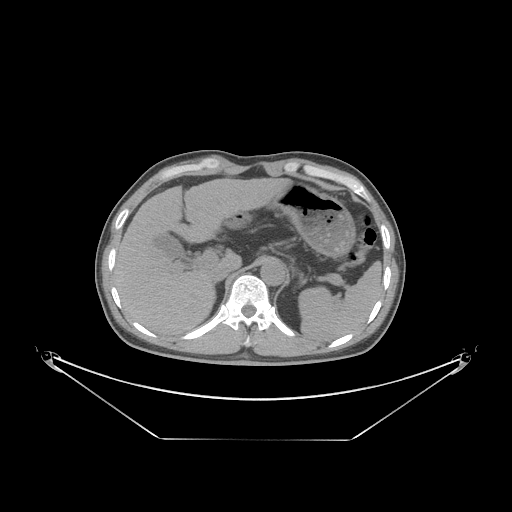

Case Study 3: Multi-Organ Segmentation

The cognition of artificial intelligence is important for computer-aided diagnostic. Multi-organ segmentation can help the machine understand the structure of the human body, which is very important for all the relevant tasks. Therefore, some research has focused on single- or multi-organ segmentation tasks, such as the liver([79, 80]) and the pancreas([81, 82]). In this case study, we use a VNet-based neural network to solve the multi-organ segmentation challenge, SegTHOR, [83]. The SegTHOR challenge includes about 40 CT images of the chest, and aims at the segmentation tasks of the heart, aorta, trachea, esophagus, and further more.

As Fig. 11 shows, The workflow of this case study includes six parts: “input”, “pre-processing”, “dataset management”, “neural network”, “visualization”, and “analysis”. The “input” includes images of the chest and annotations.

“Pre-processing” rescales the range of the image values with a window width and a window level. Then, the input images are re-sampled with the “resample” tool to change their size. The “dataset management” function subsequently splits the dataset into a training and a testing set randomly, yet reproducibly.

“Neural network” employs VNet to train and validate the model, which can be used to segment organs from the chest. Then, the segmented images can be visualized via the “organ visualization” option, and the results can be analyzed with the “result analysis” tool to generate an MS-Excel based report.

VI-3 Result and Visualization